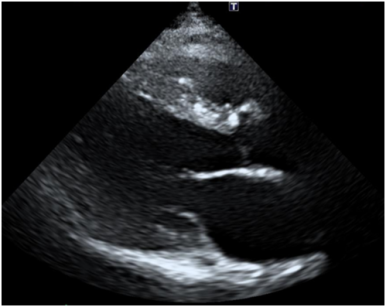

2. 심장초음파

• 심장초음파: 기능 저하 심장초음파: 기능 저하

심장초음파에서 심장기능 저하 상태인 심부전 으로 심장비대가 확인되어, 정밀 검사및 심부전 치료를 위해 상급병원으로 전원.